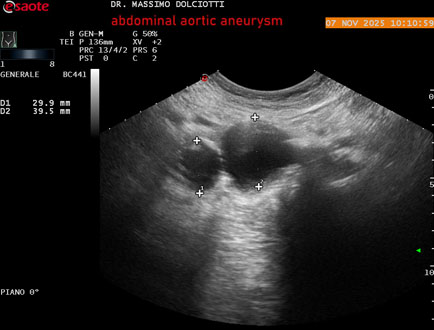

Data inserimento: 11/11/2025

Ecografia del: 07/11/2025

Strumento: Esaote MyLab Eight

Sonda: Convex Multifrequenza 1-8 MHz

Età Paziente: M 60 anni

Motivazione dell'esame: follow up per aneurisma dell'aorta addominale.

Commento all'esame: le immagini ed il video documentano la presenza dell'aneurisma dell'aorta addominale sotto-renale, con diametro antero-posteriore massimo documentato di 47 / 48 mm.

Conclusioni: aneurisma dell'aorta addominale in follow up (abdominal aortic aneurysm follow-up).

Presentazione: Dr. Massimo Dolciotti - Ancona